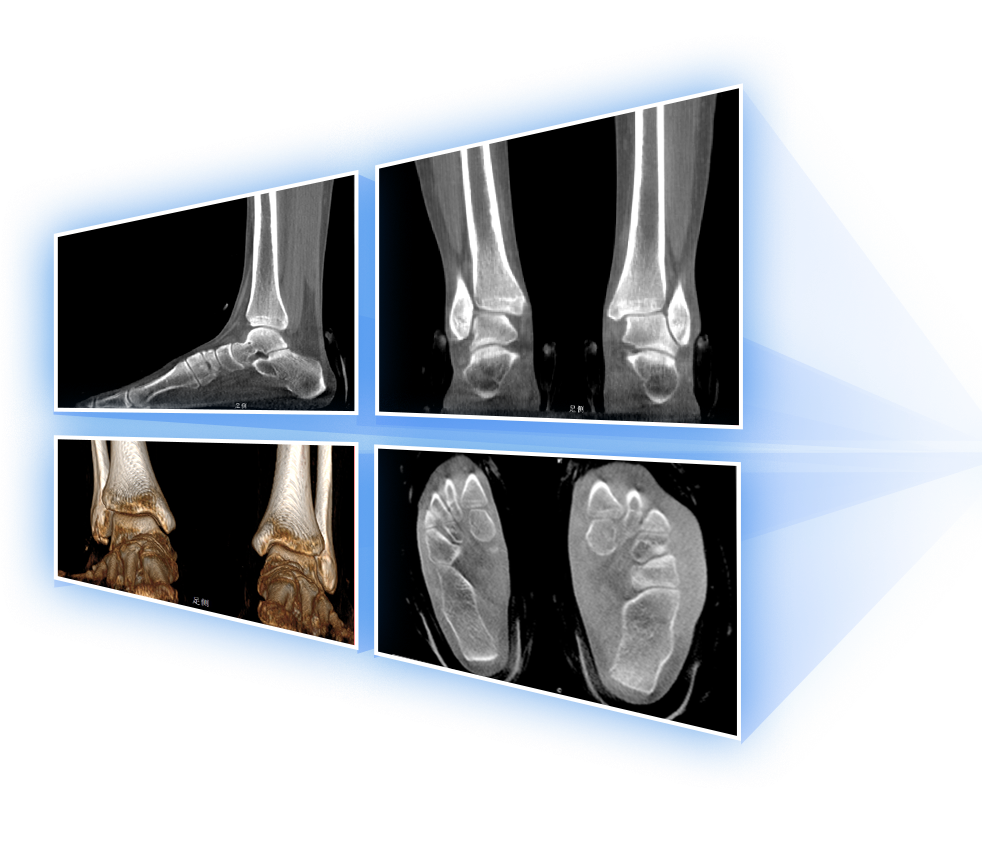

独特的负重位三维影像

填补常规CT/MR空白

助力术前规划和术后评估

• 足踝